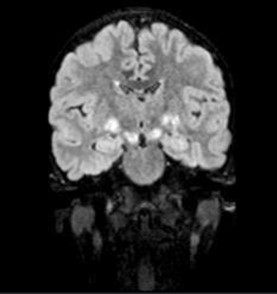

A 9-year-old male presented with a history of learning difficulties and poor scholastic performance since age six. Diagnosed with a specific learning disability-dyslexia, and Attention Deficit Hyperactivity Disorder (ADHD), he also experienced intermittent abdominal pain, enuresis, and encopresis. His development was appropriate for age. He had a borderline IQ of 75 (Wechsler Intelligence Scale for Children). He was operated for exotropia at the age six. There was no family history of neurodevelopmental or neurocutaneous disorders. Physical examination revealed short stature (Height: 128 cm, at 10th percentile), weight of 25 kg (25th-50th percentile), and a head circumference of 52 cm (50th-90th percentile). Multiple café-au-lait macules (more than 15, with only four larger than 5 mm) were noted. Dysmorphic facial features, including a flat facial profile, lowset ears, and dental malocclusion, were observed. Neurological examination was remarkable for hyperesthesia over the C6T1 dermatomes bilaterally with no other neurological deficits. Given the incomplete fulfillment of NIH criteria for café au lait macules in Neurofibromatosis Type 1, additional investigations were pursued. Slit lamp examination revealed a single iris Lisch nodule in the left eye. Both audiological and orthopedic assessments were normal. Abdominal ultrasonography and echocardiography were normal. Brain MRI identified ‘Focal Areas of Signal Intensities (FASI)’ in the bilateral globus pallidus, crus cerebri, and dentate nuclei, consistent with NF1 (Figure 1). Spinal MRI with contrast, disclosed multiple bilateral paravertebral enhancing nodular lesions in the dorso-lumbar spine and sacral canal with the largest at L4-L5 level measuring 2.6X2.4X3.2 cm in the left paravertebral region along with mild extension into the L3-L4 and L4-L5 neural foramina, consistent with plexiform neurofibromas (Figure 2). Genetic testing confirmed a heterozygous c.499del (p. Cys167ValfsTer11) pathogenic variant in the NF1 gene, affirming the diagnosis of Neurofibromatosis Noonan’s Syndrome (NFNS). The patient was initiated on methylphenidate in addition to behavioral interventions and individualized educational plan for the specific learning disability and ADHD. Neurosurgical consult for spinal plexiform neurofibromas, recommended conservative management with a trial of the novel drug, Selumetinib, a MEK inhibitor, for the spinal plexiform neurofibroma. The family received counseling on the chronic nature of the condition, the importance of close follow up, behavioral interventions for the comorbidities and the potential need for surgical intervention in the future if the spinal plexiform neurofibromas increase in size or develop a malignant transformation.

Figure 2: Coronal T1W Spinal MRI showing multiple nodular enhancing paravertebral lesions (red arrows) consistent with Spinal Plexiform Neurofibromas.